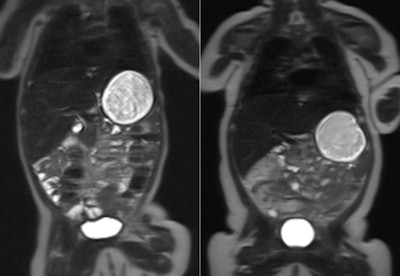

MRI scans of two babies at 10 weeks old. The child on the left was born to a healthy mother, while the child on the right was born to a mother with gestational diabetes. The white area on the outside of the body is fat tissue. Image credit: Imperial College London.Gestational diabetes affects approximately one in 20 pregnant women in the U.K. and nearly one in 10 in the U.S., wrote lead author Dr. Karen Logan and colleagues (Diabetes Care, May 12, 2016).

The babies wore special earmuffs to protect them from the noise of the scanner. Image credit: Lucinda Winckworth.Although babies born to mothers with gestational diabetes had no difference in body fat at birth when compared with those born to healthy mothers, at 2 months old, they had 16% more body fat than the control group.